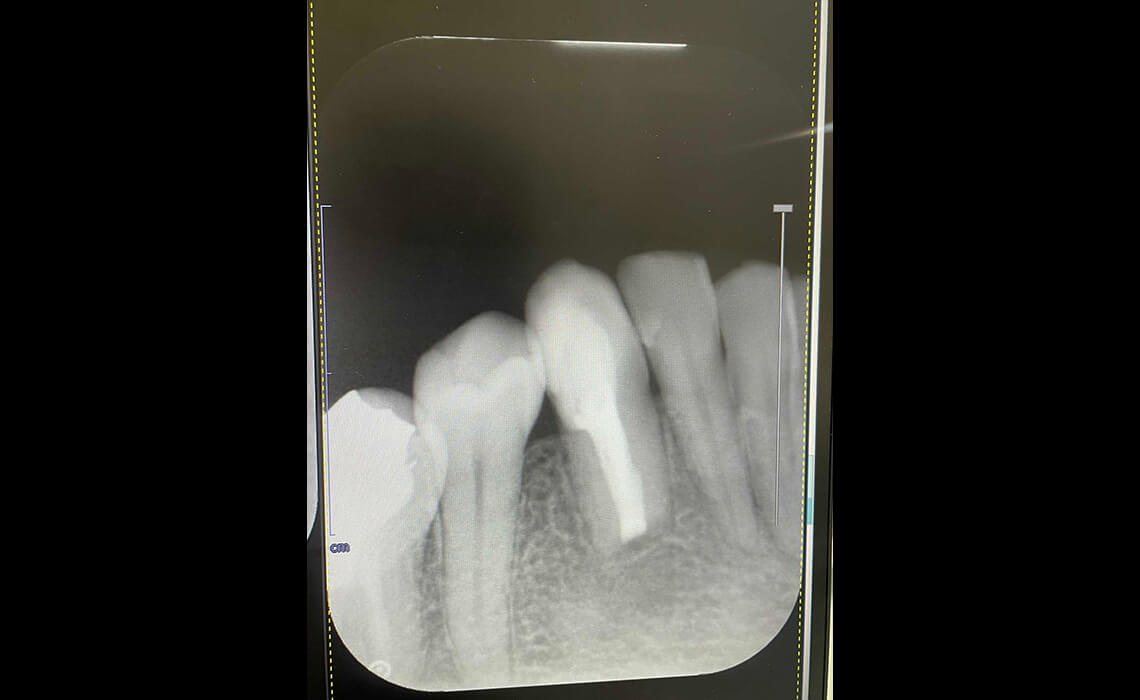

まずはカウンセリングと診査を行います。デジタルレントゲンやCTで歯の内部や根管の形を正確に把握し、治療計画を立てます。

感染が取り除けたら、MTAセメントやガッタパーチャを用いて根管を緊密に封鎖します。MTAセメントは高い封鎖性と生体親和性を持ち、歯の保存性をさらに高めます。

CASE